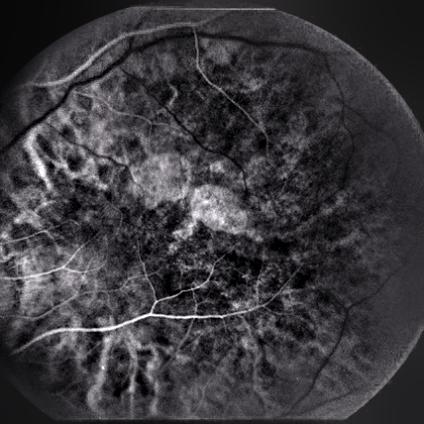

4.4 DCGANs and WGANs

In this section, DCGANs and WGANs are trained with thousands of CFP and FA images that have symptoms of drusen and GA separately; both of the models require four to six hours to train. Generated images have been diagnosed by ophthalmologists for verification. Images generated by DCGANs, which are shown in Fig. 8, cannot be identified as a valid retinal image with symptom. However, drusen and GA images generated by WGANs can be used by ophthalmologists to diagnose. In Fig. 9, generated drusen images are diagnosed as insignificant of drusen but can be identified by EyeNet. As for generated GA images in Fig. 9, irregularly shaped macular atrophy can be identified by an ophthalmologist. Macular atrophy is a distinguishable trait of GA, which means WGANs indeed learn the symptoms of drusen and GA from specific AMD and generate new images. Thus, WGANs perform better than DCGANs because of resolution. Structure of DCGANs limits the size of generated images to be 64x64, so some pathological details are lost. We choose WGANs for following experiments.

Figure 9: Drusen and GA images generated by WGANs.(a) Generated drusen CFP image. (b) Generated drusen FA image. (c) Generated drusen CFP image. (d) Generated GA FA image.

4.8 Neural Network Visualization for Retinal Images

Finally, we verified the hypothesis that vessel-based segmentation and contrast enhancement are two coherent features to decide the type of retinal diseases. Using techniques of generating CAMs introduced in [8], we visualized feature maps of the final convolutional layer of ResNet50 in Fig. 13. In our results, generated drusen images are well identified. However, generated GA images are not focused on the exact location of the symptom, but they are close. As discussed above, in the clinical diagnosis process, ”vessel patterns” and ”fundus structure” are the most crucial features for identifying the symptoms of different diseases. These types of features cover more than 80% of retinal diseases [27, 28].

Figure 13: Generated images and their CAMs. (a) Original drusen image (CFP). (b) Generated image of (a) by WGANs. (c) CAM of (b). (d) Original GA image (CFP). (e) Generated image of (d) by WGANs. (f) CAM of (e). (g) Original GA image (FA). (h) Generated image of (g) by style trnasferring. (i) CAM of (g).

We have implemented style transferring, DCGANs and WGANs to generate disease images that are detailed to capture different stages of AMD. Symptoms of images are drusen and GA; both FA and CFP images are generated. Images from DCGANs are difficult to be identified due to limit of resolution. However, images from style transferring and WGANs are easier to identify by ophthalmologists,and generated images preserve pathological details. EyeNet is used to predict the disease label, and results of generated drusen images are similar to original images. However, generated GA images are more distant compared to original images, because of the small number of GA images used during training EyeNet. This phenomenon shows that generated new images can be fed into the classifier to improve it. Also, CAMs are useful for extracting label-specific features. In Fig. 13(c),(f) and(i), warmer color parts are located in the well-demarcated areas or spots, which represents disease features that are close to those parts.